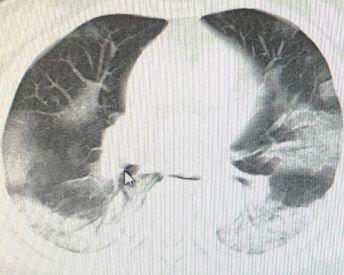

新冠病毒在全球持续蔓延,云南省作为中国的西南重要省份,疫情防控工作备受关注,本文将围绕云南省新冠肺炎最新确诊情况进行深入分析,探讨当前疫情防控形势及应对策略。

截至最新数据,云南省累计报告新冠肺炎确诊病例数量,在全省人民的共同努力下,疫情得到了有效控制,随着全球疫情的持续演变,云南省疫情防控工作仍面临严峻挑战。

1、近期新增病例情况:云南省新增新冠肺炎确诊病例数量有所波动,需关注疫情高发地区,加强防控力度,防止疫情扩散。

3、变异株情况:随着全球疫情的演变,云南省也出现了多种新冠病毒变异株,变异株的传播速度、致病力及免疫逃逸能力可能有所增强,给疫情防控带来挑战。